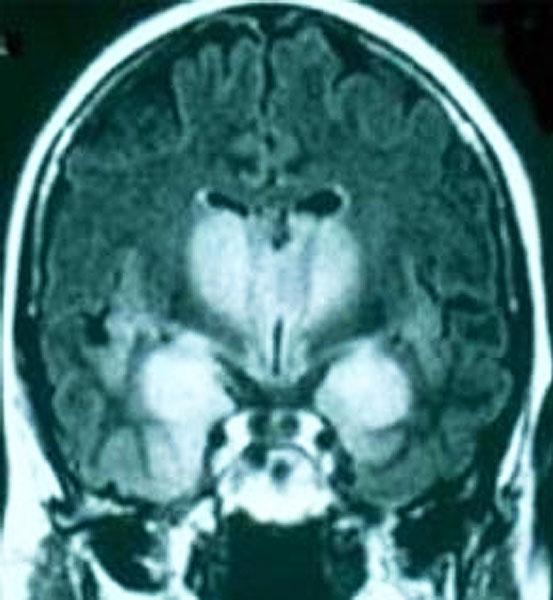

C71.9 Злокачественное новообразование головного мозга неуточненной локализации

Глиоматоз головного мозга